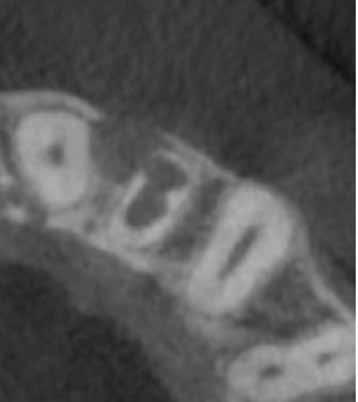

A 28 éves pácienst gyulladásos IRR kezelése céljából irányították a rendelőnkbe. A jobb felső nagymetszőfogáról készített periapikális röntgenen egyértelműen látható volt a lézió. A várható prognózis megállapítása, valamint kezeléstervezés céljából az érintett területről CBCT-felvétel készült (8. a–e ábra). A háromdimenziós képen látható volt a gyökér

8. a–e ábra: A kiindulási röntgen (a) és a kiindulási állapotról készített CBCT-felvétel (b–e). A felvételen jól látható a csatornafal és a bukkális kortikális perforációja. – 9. a–b ábra: A műtét előtt (a) és a lebeny felemelését követően látható állapot (b). – 10. a–d ábra: A granulációs szövet eltávolítása. 11. a–b ábra: A gyökércsatorna átöblítése. – 12. a–b ábra: A gyökértömés elkészítése. – 13. a–c ábra: A reszorbtív üreg bioanyaggal való feltöltése és a kollagénszivacs elhelyezése. – 14. a–b ábra: Posztoperatív röntgen (a), a varratok behelyezését követően látható klinikai helyzet (b).

labiális falán lévő perforációs nyílás, valamint az ezt körülvevő bukkális kortikális destrukciója.

A terület sebészi feltárását a bal felső nagymetszőfogtól a jobb felső szemfogig intrasulcularisan vezetett metszésből végeztük el. A lebeny elemelését követően egy exkavátor segítségével eltávolítottuk a reszorbciós üreget kitöltő granulációs szövetet (9–11. ábra), majd hagyományos protokollt követve elvégeztük a gyökércsatorna kemomechanikai megmunkálását.

A csatornát először passzívan levezetett kézi tűk segítségével szondáztuk, majd gépi tágítók alkalmazásával a teljes munkahosszon feltágítottuk, ezalatt nátrium-hipoklorittal öblítettünk, amelyet manuális agitációval aktiváltunk. A csatorna kémia tisztítását az előző esetnél leírt protokollnak megfelelően végeztük el.

A gyökértömés elkészítése során meleg vertikális kompakciós technikát alkalmaztunk, sealerként pedig AH Plus sealer-t (Dentsply Sirona) használtunk. A reszorbciós üreget gyors kötési idejű MTA-val (Mineral Trioxide Aggregate; Harvard Dental) töltöttük fel. A léziótól koronális irányban elhelyezkedő gyökércsatorna-szakaszt meleg guttaperchával zártuk, majd az MTA-val kitöltött üregre egy kis darab kollagénszivacsot helyeztünk és a lebenyt varratok segítségével eredeti pozíciójában rögzítettük (12. a–b; 13. a–b. ábra). A fog koronai részét Gradia kompozit tömőanyaggal állítottuk helyre (GC; 14. a–b; 15. ábra). Kontrollvizsgálatra két (16. a–b ábra), és négy évvel (17. a–b ábra) később került sor. A kontrollfelvételeken a bukkális kortikális jelenléte volt észlelhető. A fog körüli parodoncium egészséges volt, valamint a páciens sem számolt be tünetekről.